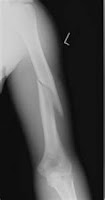

| Broken Humerus |